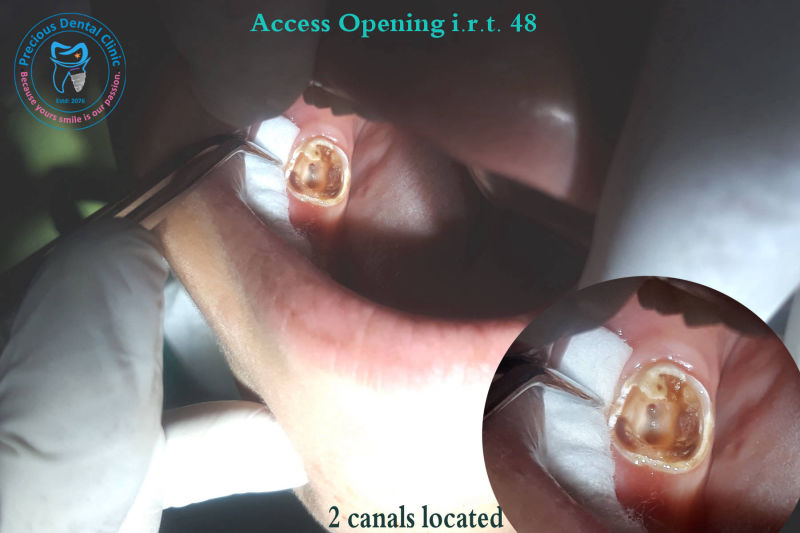

Root Carries AO with Canals